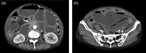

Subcapsular liver hematoma after extracorporeal shock wave lithotripsy, a rare complication

Gabriel A Molina and others

Journal of Surgical Case Reports, Volume 2019, Issue 4, April 2019, rjz114, https://doi.org/10.1093/jscr/rjz114